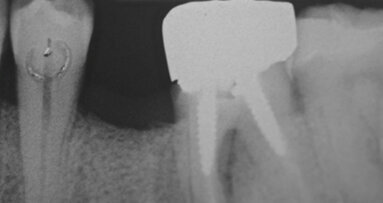

I lembi sono stati poi suturati a livello dell’osso (Gore-Tex®, 4.0, Gore, Newark/ NJ, USA) senza la necessità di ottenere una chiusura completa (Fig. 3). In fase postoperatoria è stato prescritto un antinfiammatorio (Nimesulide 100 mg, 2 volte al giorno per 3 giorni), un analgesico (Paracetamolo 500 mg, 1 compressa ogni 8 ore per 3 giorni) e clorexidina 0.12%, e fornita istruzione completa all’igiene orale. La sutura è stata rimossa dopo 10 giorni. A 3 e a 6 mesi sono state eseguite le radiografie periapicali parallele.

Le radiografie eseguite immediatamente dopo l’intervento chirurgico con la tecnica GBR hanno indicato che l’alveolo post-estrattivo era stato adeguatamente zeppato con granuli di osso bovino decellularizzato (Fig. 7). Il richiamo a 6 mesi, ha mostrato tessuti molli in buona salute senza la presenza di segni di infiammazione (Fig. 8). La radiografia periapicale ha mostrato la perfetta guarigione dell’alveolo post-estrattivo (Figg. 9, 10). Anche durante l’esposizione ossea per il posizionamento dell’impianto, l’osso appare in buona salute e non sono presenti granuli di biomateriale non integrato. La membrana di pericardio bovino è completamente riassorbita (Fig. 11).